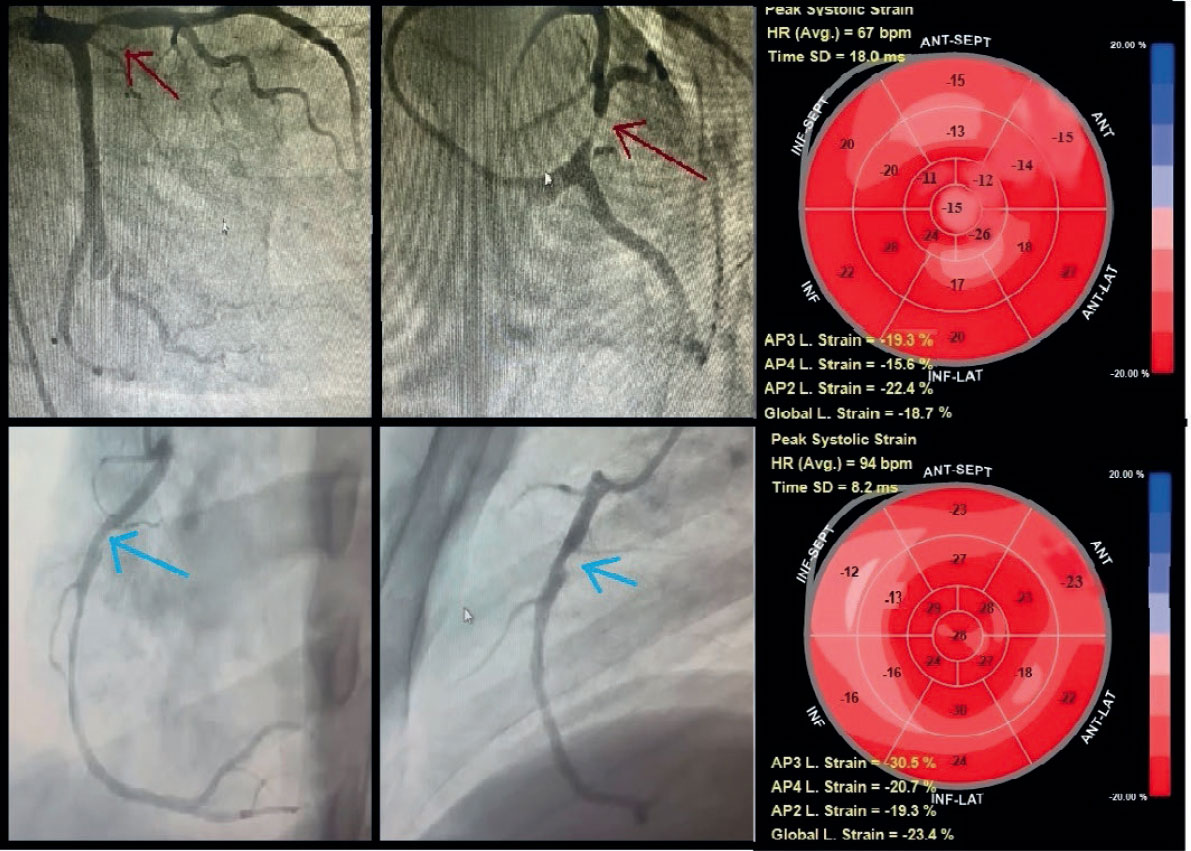

Guided by the detected cutoff of ≥ -16% for the optimal sensitivity and specificity of RLS, the predictive role of TLS in stable CAD for identifying the location and severity of significant coronary artery lesions with ≥ 70% diameter stenosis was explored (table 4). The ROC curve analysis of the RLS at a cutoff of ≥ -16% demonstrated that the optimal number of impaired segments that could predict the location and severity of significant coronary lesions with ≥ 70% diameter stenosis was ≥ 3 impaired segments out of the 7 territorial segments of LAD to predict proximal or significant lesion in the mid-LAD and ≥ 3 impaired segments among the 5 territorial segments of either the LCx or RCA to predict proximal significant lesion in the LCx or RCA (figure 4).

Figure 4. Territorial longitudinal strain of study participants with stable coronary artery disease. Top row: representative study participant with significant proximal left anterior descending coronary artery lesion (≥ 70% diameter stenosis; red arrow). Global longitudinal (L) strain was -18.7%. Seven segments within the left anterior descending coronary artery territory (anteroseptal, anterior regions, and apex) demonstrated impaired strain (≥ -16%), consistent with a true-positive finding, whereas left circumflex and right coronary artery territories showed preserved strain (< -16%), consistent with true-negative findings. Bottom row: representative of a study participant with a significant proximal right coronary artery lesion (≥ 70% diameter stenosis; blue arrow). Global longitudinal strain was -23.3%. Four segments within the right coronary artery territory (mid, basal inferior, and inferoseptal) demonstrated impaired strain (≥ -16%), consistent with a true-positive finding, whereas left anterior descending artery and left circumflex artery territories showed preserved strain (< -16%), consistent with true-negative findings.